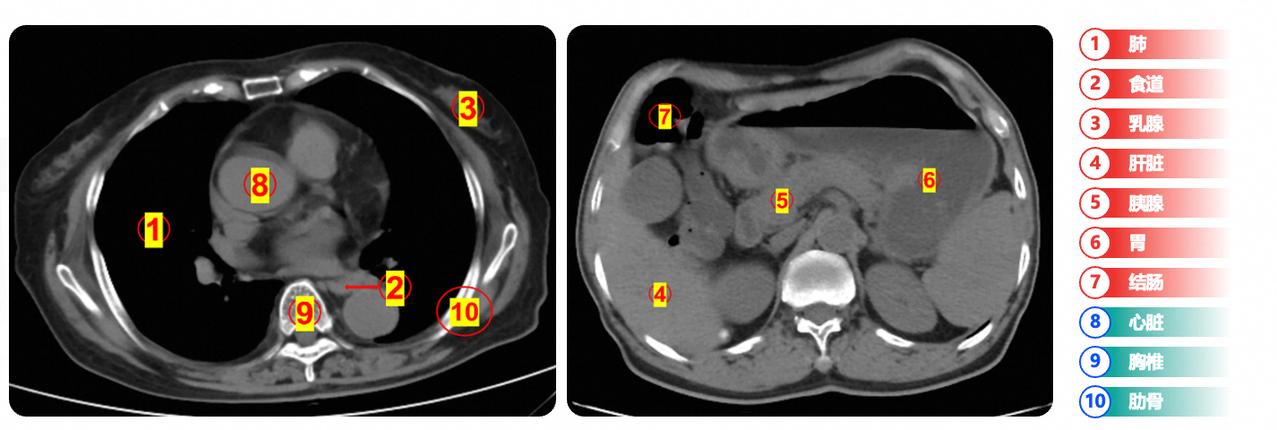

终于不用谈癌色变了,答案就藏在《自然医学》杂志的三篇论文里。 科普一个关于癌症的数据。有调查机构的数据显示,目前我国每年新发癌症病例约为312万例,平均每分钟就有6人被诊断为癌症,每年因癌症死亡病例达270万例。 听到这个数据可能很多人会吓一跳,但确实就是正在发生的事实。不过来自中国的团队也在这方面取得了一些进展,阿里最新医疗AI研究成果已经连续三次发表在了全球医学顶刊《自然·医学》上。 这项成果在“癌症之王”胰腺癌的早筛上实现了重大突破。这是全球医学界多年未能攻克的难题。要知道,要知道,胰腺癌之所以凶险,正是因其早期极难被发现,超过80%的患者确诊时已回天乏术。 不仅如此,在最近的上海进博会上,也传来一个令人振奋的消息:医疗设备领域的百年巨头GE医疗,正式宣布与阿里达摩院签约,引进了“一扫多查”医疗AI技术。这意味着,今后有可能在GE最先进的CT机上,将搭载中国的AI技术,仅需一次扫描,就能精准捕捉到早期胰腺癌、胃癌等病灶的蛛丝马迹。 为何这家见证了整个医疗影像发展史的百年企业,会选择阿里? 答案藏在三篇论文里。在全球医学顶刊《自然·医学》上,阿里达摩院的医疗AI研究成果已经连续三次获得发表——尤其是在“癌症之王”胰腺癌的早筛上实现了重大突破。这是全球医学界多年未能攻克的难题。要知道,胰腺癌之所以凶险,正是因其早期极难被发现,超过80%的患者确诊时已回天乏术。 GE医疗的选择,本质上是对最顶尖技术实力的最强认证。这家见证了整个医疗影像发展史的百年企业,比谁都清楚什么样的技术才能真正对患者有帮助。 可见,中国科技正在用实力走出一条独特的创新之路。不仅让技术进入寻常百姓家,还在关乎人类健康的共同命题上,从“追随”走向“并行”,甚至“引领”。而这,或许正是我们每个人未来健康的希望所在。